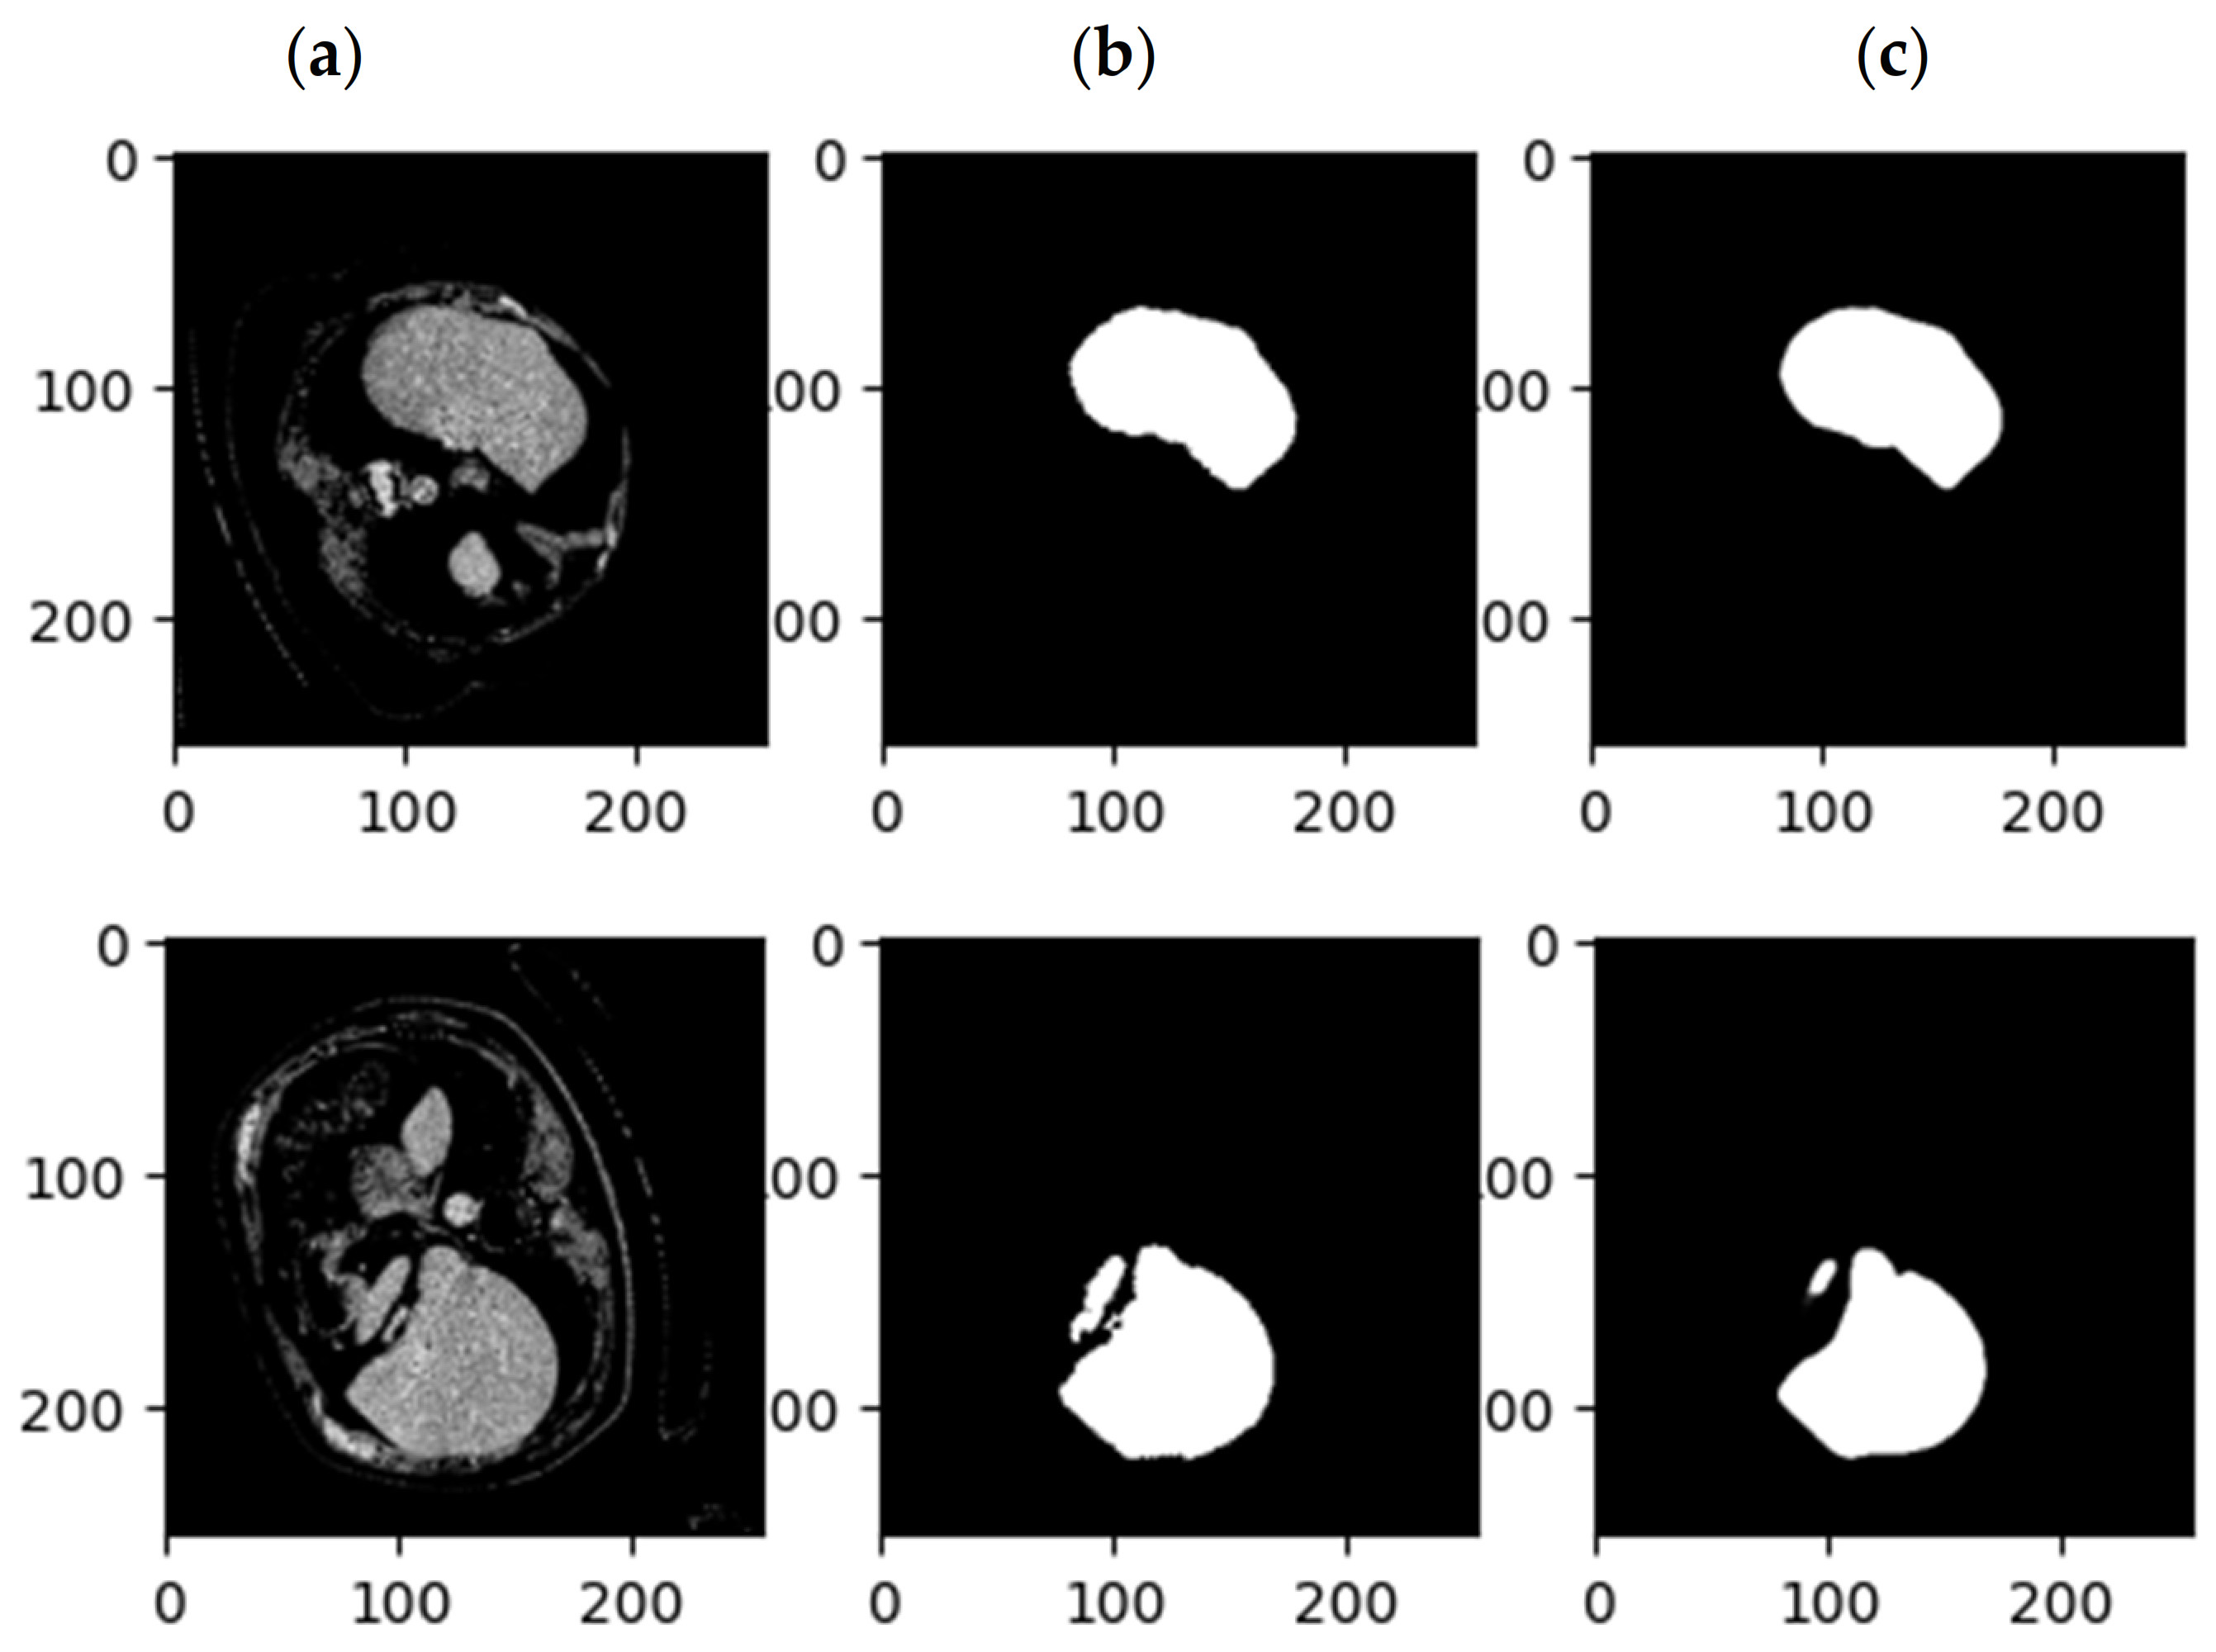

3.1. Images Preprocessing

3.2. Graph Embedding Stage